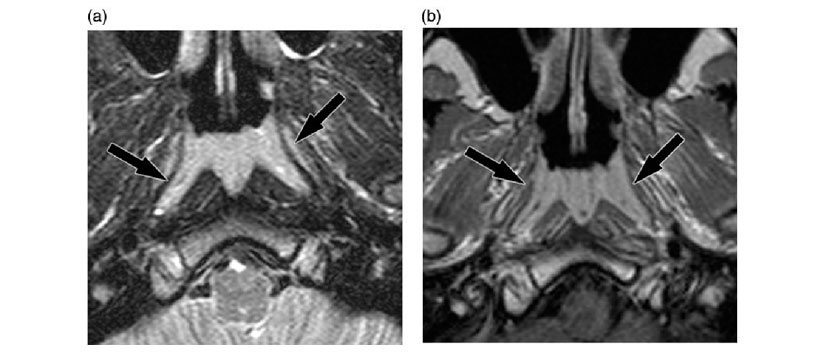

Debido a la involución, el tejido linfático nasofaríngeo generalmente no se encuentra en adultos mayores de 30 años a 40 años de vida. Sin embargo, ocasionalmente se ha reconocido la HA después del año 50 o 60, a ésta edad, la diferenciación entre la HA y las lesiones nasofaríngeas malignas puede ser difícil. Anteriormente, las apariciones de imágenes de resonancia magnética (RM) de HA se han descrito en solo unas pocas series. Además, la frecuencia de HA no se ha informado anteriormente. Típicamente, la HA se manifiesta como una lesión simétrica con franjas y quistes de retención, sin embargo, la HA también puede presentar engrosamiento de la mucosa asimétrica y puede ser diagnosticada erróneamente como neoplasia maligna.

En las imágenes T1-w, la mayoría de las lesiones (95,4%) fueron hipointensas en comparación con la musculatura adyacente. En las imágenes saturadas de grasa T2-w, el 82,4% de las lesiones eran hiperintensas. Después de la administración intravenosa de medio de contraste, la mayoría de las lesiones mostraron una ligera mejoría (58,6%). Se observó una mejora moderada en el 32,4% y se identificó una mejora marcada en el 9,0%. En el grupo de 0 a 9 años de edad, la mayoría de las lesiones mostraron una leve mejoría. Se identificaron quistes dentro de la HA en 433 casos (35.9%). La frecuencia de los quistes aumentó continuamente con la edad, es decir, del 10,9% al 65,2%.